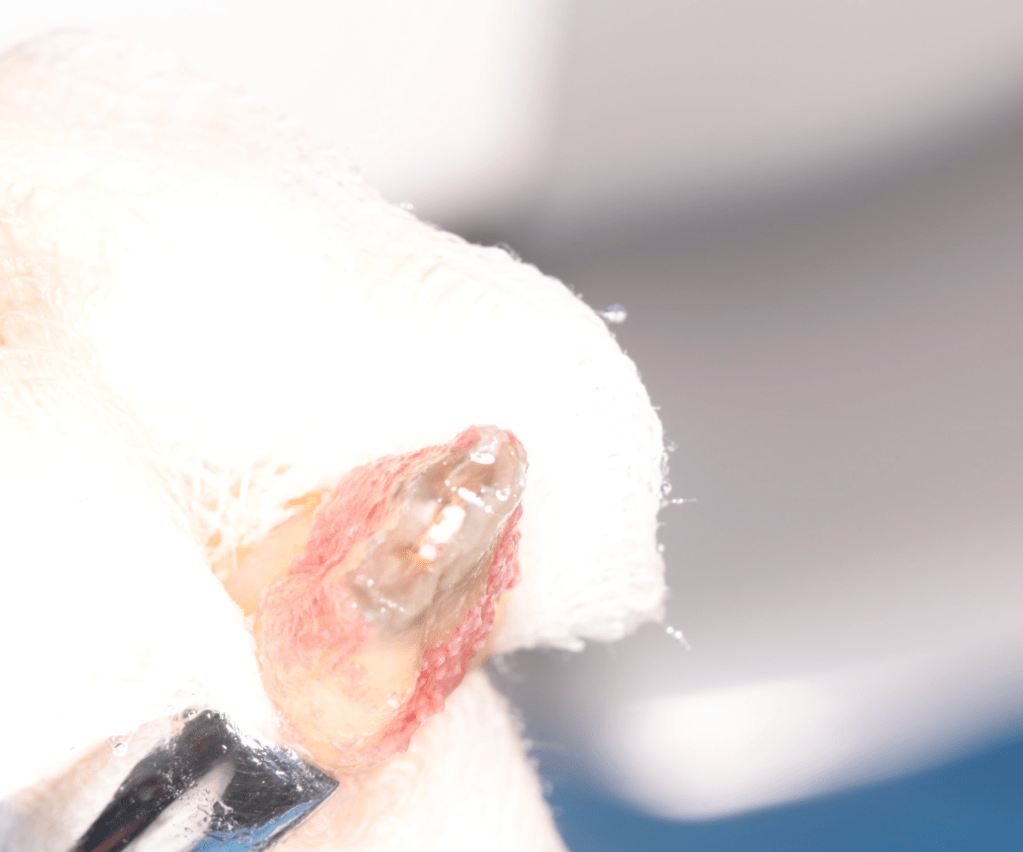

Autotansplantes

REIMPLANTES

Intencional por dificil acceso coronal y quirúrgico

Reinplante por fracaso de tratamiento

Reimplante, istmo apical, curación cortical palatina 1 año